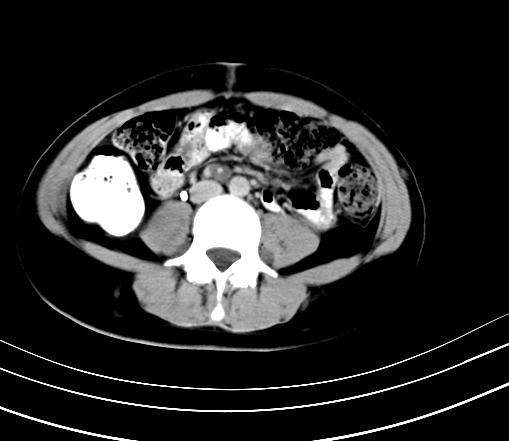

静脉期